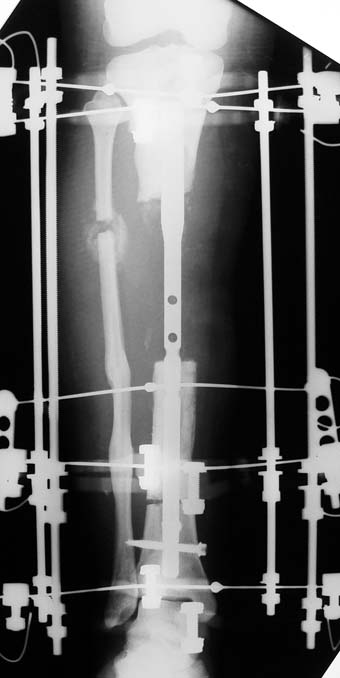

Appropriate radical debridement necessitates excision of all necrotic bone and soft tissues, and frequently causes instability at the involved extremity. The remaining bone and soft tissue defect has to be fixed and reconstructed. The distraction osteogenesis method of Ilizarov is used successfully for achievement of union, correction of the deformity, elimination of limb length inequality and reconstruction of segmental bone defects.

The duration of external fixation (external fixation index) depends on the amount of distraction required, and the extremity is prone to complications during this period. After the distraction phase is completed, the external fixator remains in place during the consolidation phase, which lasts twice as long as the distraction phase; but this period is hardly tolerated. If the external fixator is removed before sufficient consolidation is achieved, fractures, deformity and shortness will be the result. In our department, ‘lenghthening over nail’ method is used in order to decrease the external fixation index and increase patient comfort and activity level. In this method, the intramedullary nail is statically locked after the completion of the distraction phase, and external fixator is removed. The extremity is stabilized by the intramedullary nail during consolidation phase. In this way, complications due to long external fixation index or early removal of the external fixator are avoided.